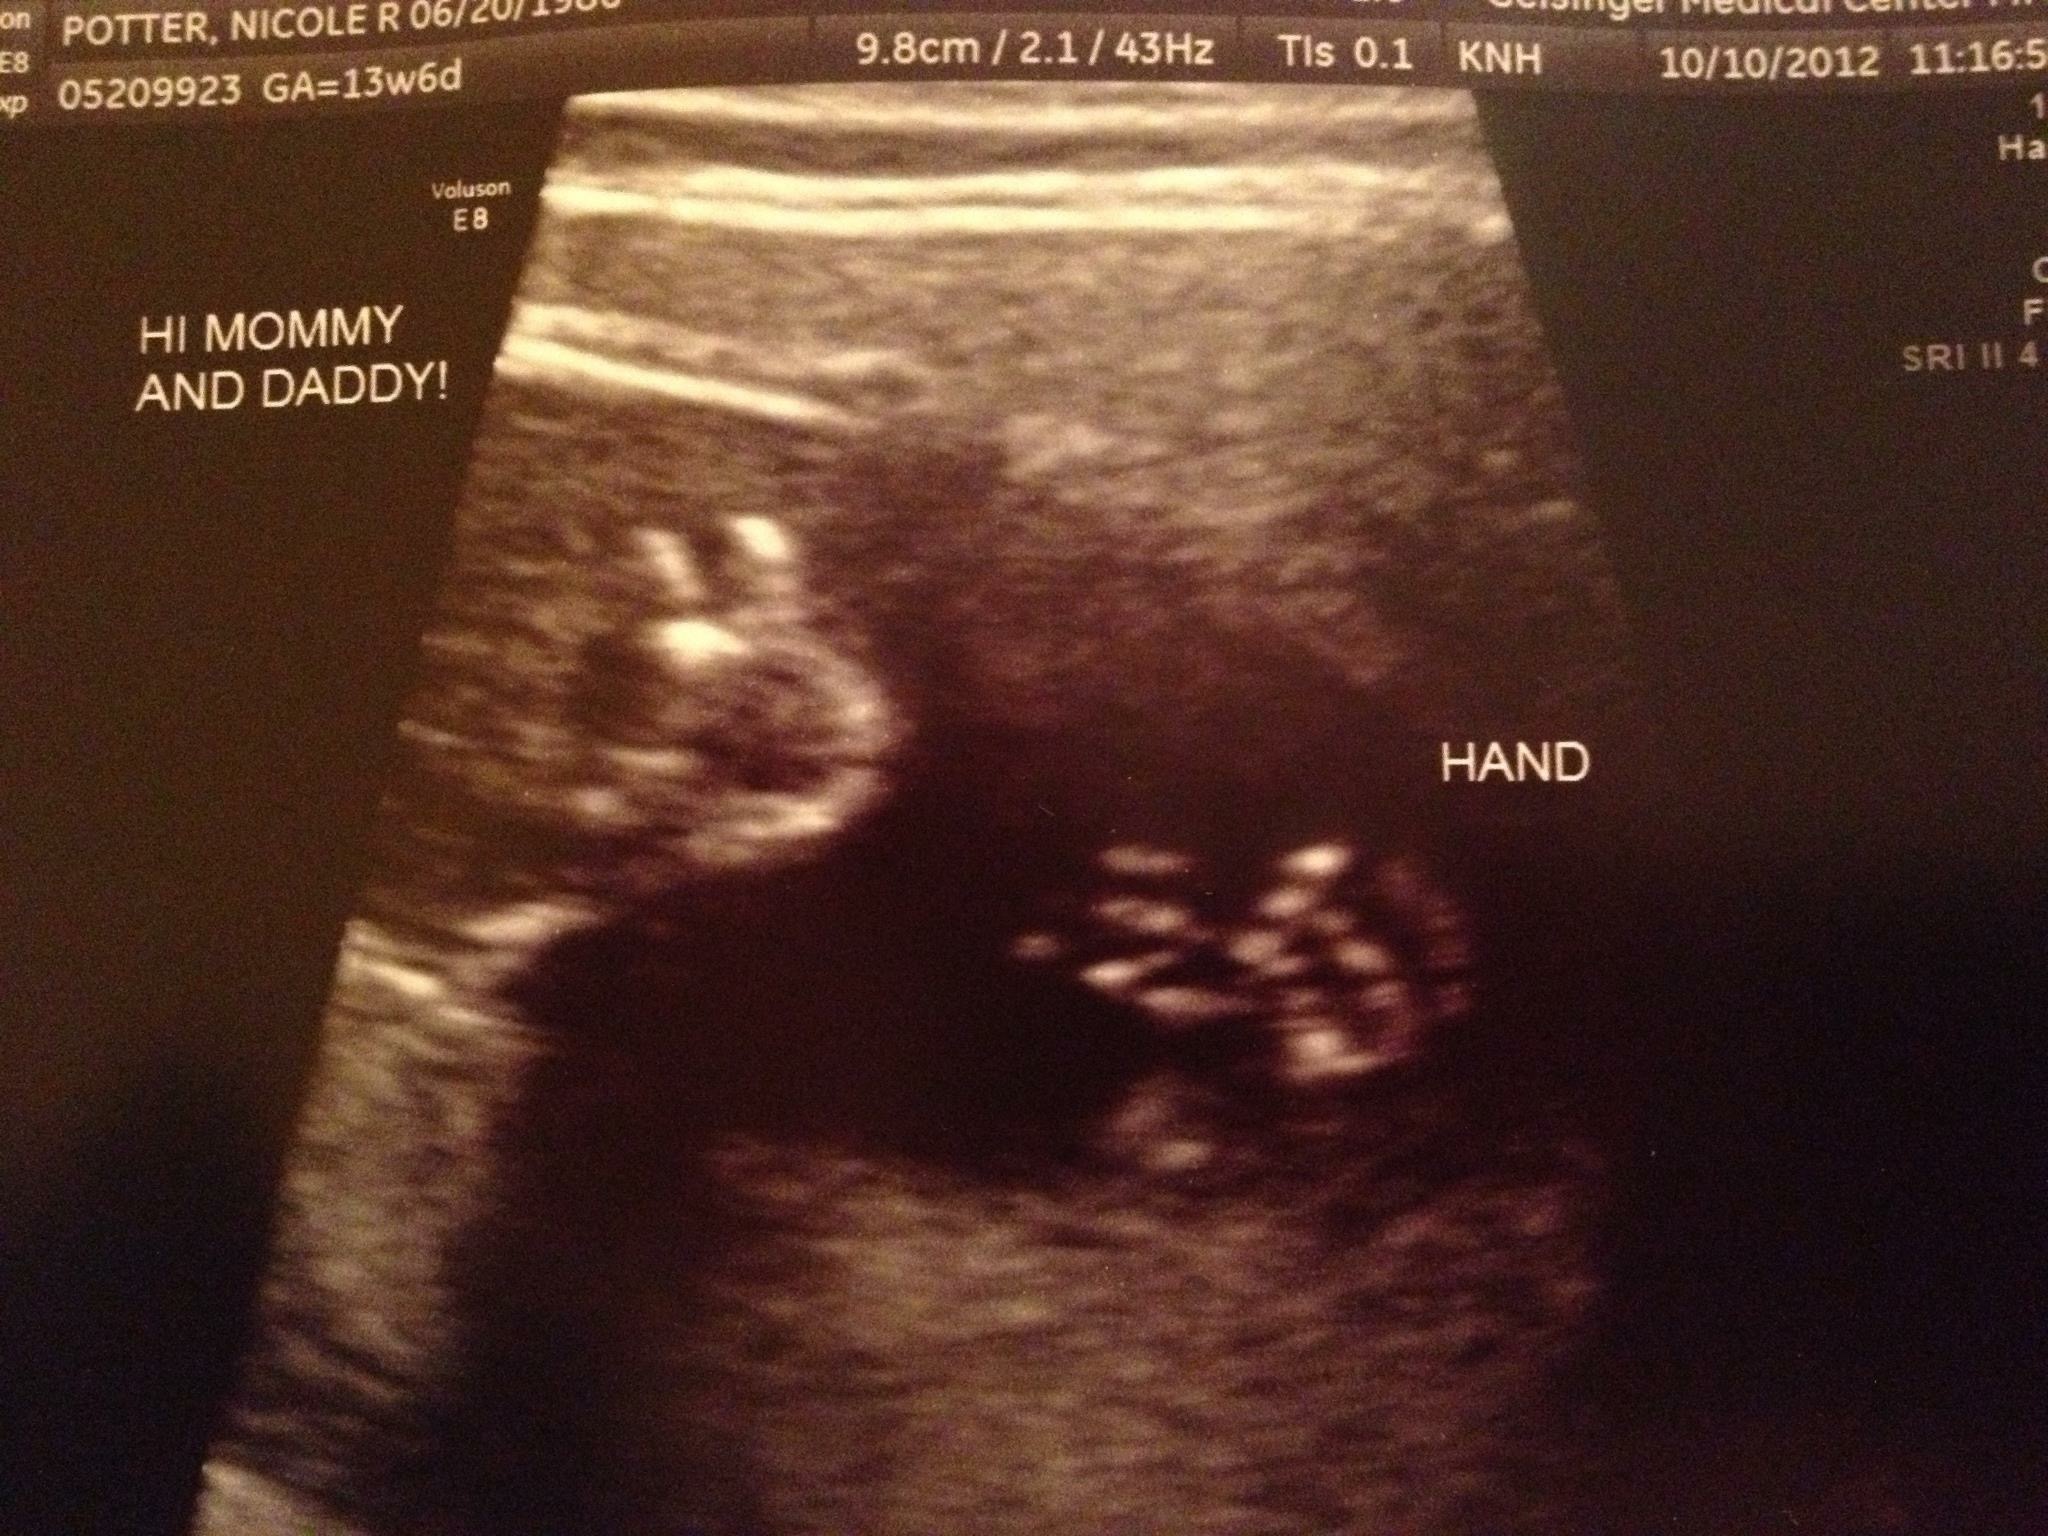

Hi all! I should preface this question with a little information - This is my first pregnancy, and I worry A LOT. Like, everything makes me anxious. I had a great 10 week ultrasound yesterday which put my mind at ease, but then I got my referral for my nuchal translucency US, which gave me something new to worry about!

Anyway, I understand this screening needs to take place between 11-14 weeks. The soonest they are able to get me in is at 13 weeks, 4 days. Clearly this is within the 14 weeks, but I can't help but wish they could see me sooner. I was told that after 14 weeks, the screening is far less reliable in detecting potential issues.